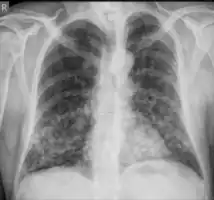

In the juvenile form, lung abnormalities are shown in high-resolution CT scans of the lungs, whereas in the chronic form plain X-rays may show interstitial and alveolar infiltrates in the central and lower lung fields.[14]

Chest X-ray: Nodular shadows both lungs